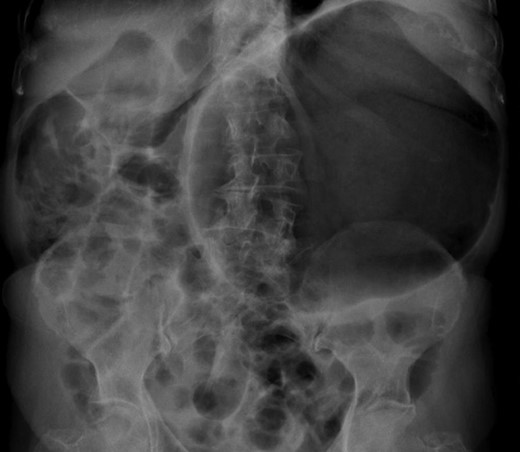

The patient’s leucocyte count and serum amylase presented mildly elevated. Chest radiograph revealed an elevated left hemi-diaphragm. Abdominal radiographs demonstrated a spherical stomach, presupposing an upward position of the pylorus (Fig. 1).

Abdominal radiograph, demonstrating a spherical stomach, presupposing an upward position of the pylorus.